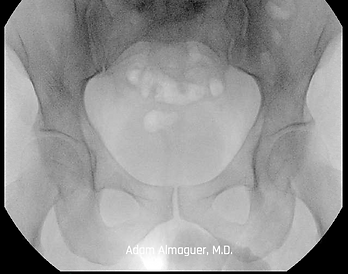

Bilateral Hip Dysplasia

Hip dysplasia occurs when the femoral head (ball) is improperly seated in the acetabulum (hip socket). Over time this misalignment causes pain, labrum damage, and cartilage wear. While most cases of hip dysplasia are caught during infancy, mild or “shallow” cases of dysplasia often are not diagnosed until young adulthood.

Periacetabular osteotomy (PAO) is a surgical procedure that reorients the patients pelvis into the correct position. Cuts are made to the bone to reposition the acetabulum into the correct position. Screws are then placed to maintain this position. This correction reduces pain and wear and tear of the hip joint which prolongs the need for a hip replacement.